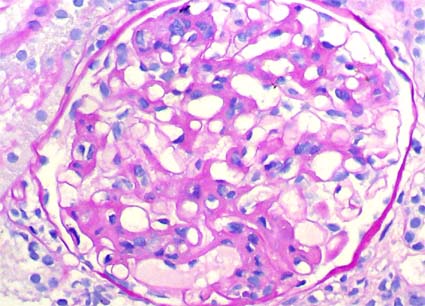

Con diagnóstico de LES se hace

biopsia renal para determinar compromiso por la enfermedad. Observe

las imágenes.

Figura 1.

H&E, X200.